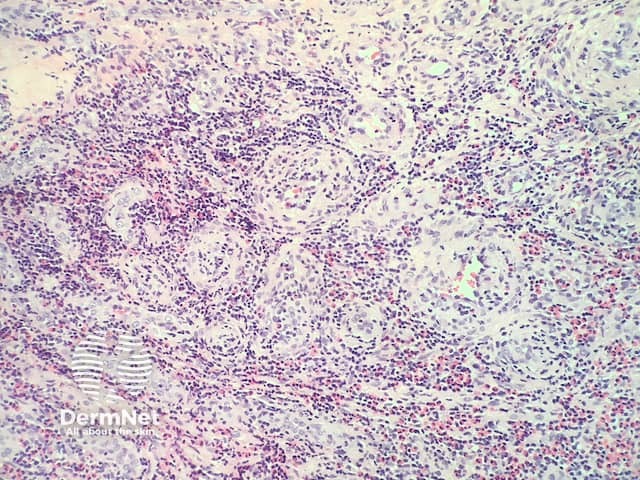

In epithelioid haemangioma, histopathologically there is a proliferation of blood vessels with epithelioid endothelial cells (figures 1,2). The endothelial cells are plump and have abundant eosinophilic cytoplasm sometimes resembling histiocytes (best seen in figure 2). As the endothelial cells are so plump, sometimes it is difficult to appreciate vascular spaces and the aggregates may resemble granulomas. Accompanying the vascular proliferation are collections of lymphocytes an numerous eosinophils (figures 1,2).

Figure 1